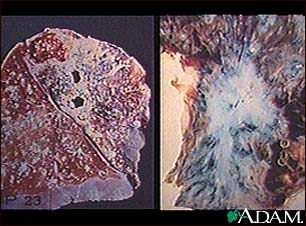

Tuberculosis in the lung

Tuberculosis is caused by a group of organisms Mycobacterium tuberculosis, M. bovis, M. africanum and a few other rarer subtypes. Tuberculosis usually appears as a lung (pulmonary) infection. However, it may infect other organs in the body. Recently, antibiotic-resistant strains of tuberculosis have appeared. With increasing numbers of immunocompromised individuals with AIDS, and homeless people without medical care, tuberculosis is seen more frequently today. (Image courtesy of the Centers for Disease Control and Prevention.)